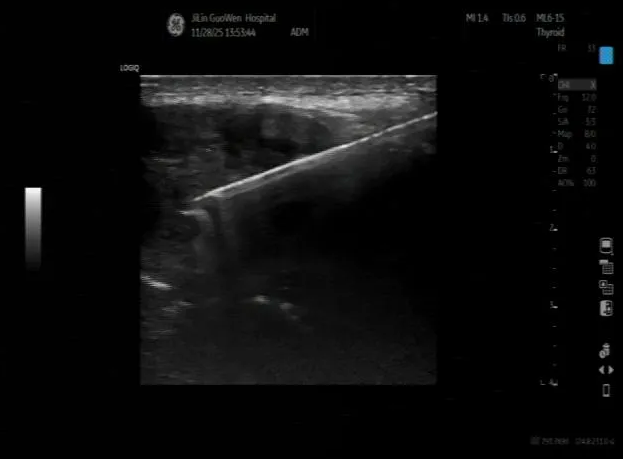

为明确肿块性质,超声科为刘先生实施超声引导下肿物穿刺活检,病理结果显示为“转移性低分化癌”,结合免疫组化,考虑为肝脏来源的肝细胞肝癌(3级)。